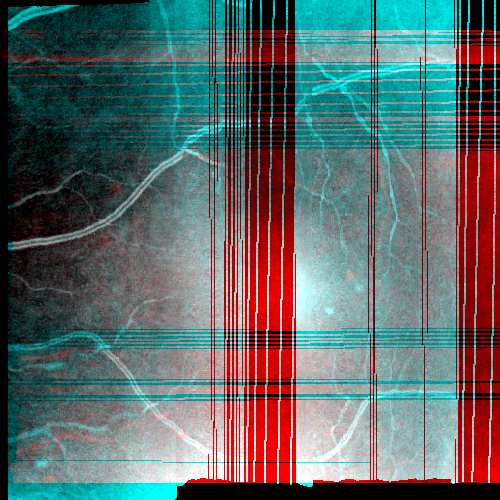

Images and estimated displacements are shown for a representative scan in Figureย 3. Tiny discontinuities prove absence of overregularization, and consistent transverse vibration indicates partial correction of ocular tremor. For quantitative analysis, we computed the median distance between the aligned A-scan displacements, and the fraction of displacements with a distance above 0.5 (problematic for supersampling) and 1 pixels (misalignments). The first and last 5% of B-scans were excluded, because they might not overlap with the orthogonal data, preventing registration. As the distributions are heavily skewed, we present box plots in Figureย 4. The three outliers in each direction in the right plot originate from the same subject, which is shown in supplementary Figureย 6. It is critical to note that the parameter density (B-scan rate 205 Hz) of the hermite splines is insufficient to fully correct ocular tremor (frequency up to 100 Hzย [16]). Therefore, this aperiodic, wave-like motion (amplitude 30โฒโฒ 1.6ย ยตm on the retinaย [16]) cannot be fully corrected, and neither is fully represented in the reproducibility error. In the transverse directions, this puts a lower accuracy limit on the evaluation scheme, but it is small compared to the pixel spacing (12ย ยตm). Using an Nvidia RTX 5000 GPU, the median and maximum runtime in the test set, excluding disk I/O which is irrelevant in clinical routine, was 8.6ย s and 31.3ย s. Tableย 1 compares average runtimes of various methods. Lastly, registration of individual B-scan repeats is demonstrated on a swept-source scanner in Figureย 5.